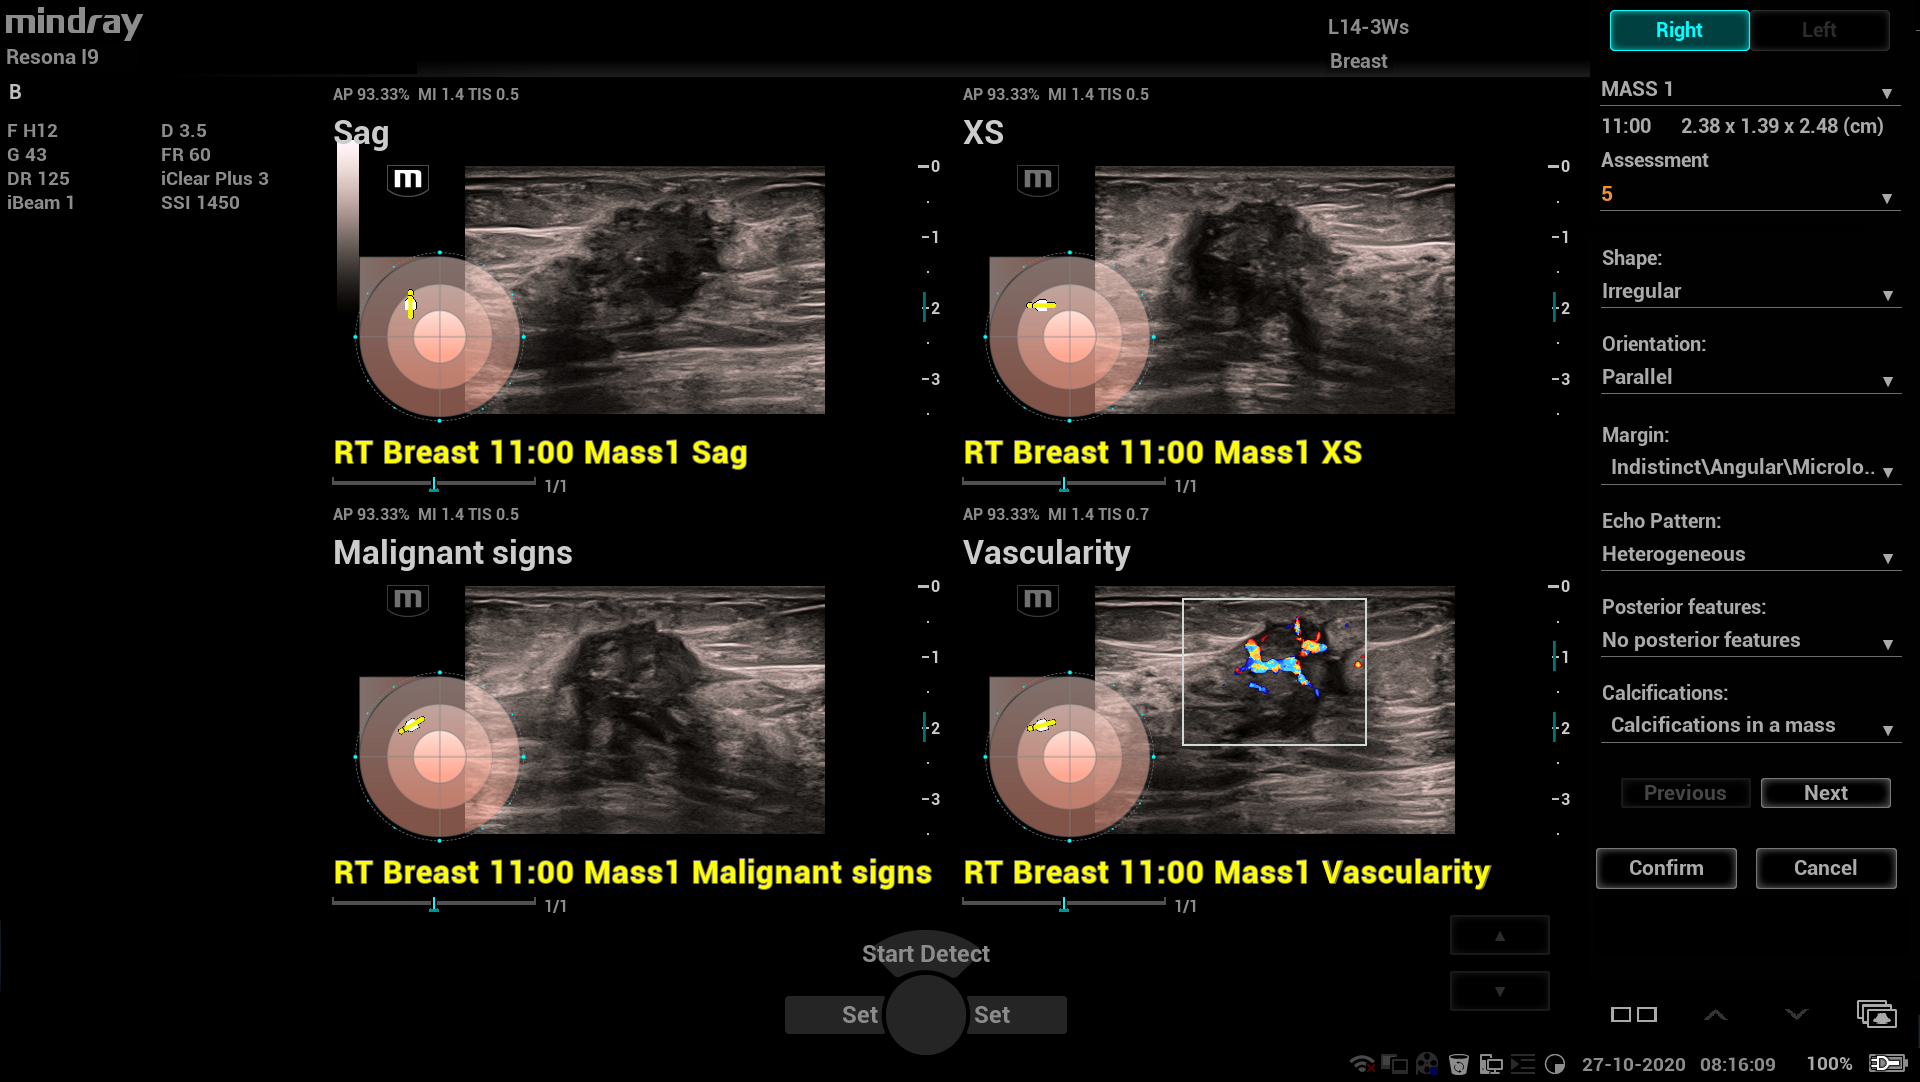

Smart Breast - Auto protokol na skenovanie prsníkov a analýza BI-RADS

Smart Brads – software umelej inteligencie: Automatické vyhľadanie lézie a jej ohraničenie. Štandardizovaný protokol detekcie lézií v oboch rovinách. Automatická B-RADS analýza. Presná a plne automatická detekcia lézií s obkreslením a pomeraním, B-RADS analýzam a vytvorenie report. Urobí vaše klinické rutinné UZV skenovanie prsníka PRESNEJŠIE, RÝCHLEJŠIE a JEDNODUCHŠIE.

Smart Breast - Auto protokol na skenovanie prsníkov a analýza BI-RADS